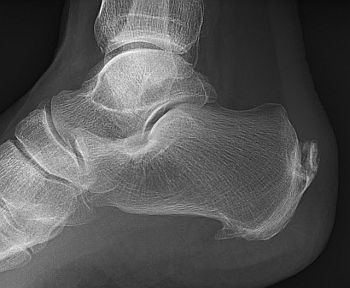

Durerea in calcai si pintenii calcaneeni

Fasceita plantara este cea mai comuna afectiune care cauzeaza durere la nivelul calcaneului in portiunea unde calcam. Ea este si cea mai comuna cauza a formarii pintenului calcanean la acest nivel. Aceasta reprezinta inflamatia fasciei plantare la locul de insertie a sa pe calcaneu.

Pintenii calcaneeni sunt un efect al fasceitei plantare. Cauzele principale ale durerii de calcai sunt fasceita plantara si tendinopatia ahileana sau maladia Haglund pentru ciocul de deasupra calcaiului, sau din spate, nu ciocul in sine, din talpa.